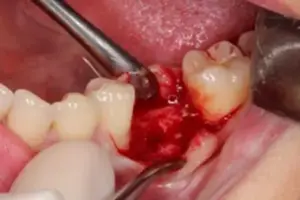

Dort, wo das Implantat gesetzt werden soll, wird das Zahnfleisch etwas zur Seite geschoben, damit ich eine gute Sicht auf den Knochen erhalte. Siehe Bild 3.

Bild 3: Zahnfleisch wird zur Seite geschoben